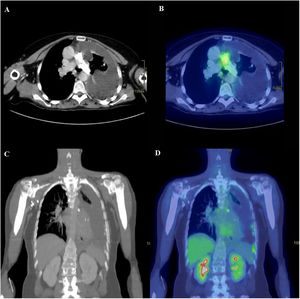

Se solicitó una nueva TC de tórax sin contraste intravenoso en la que persistía la ocupación de la luz de la arteria pulmonar principal izquierda. En esta ocasión, se pudo apreciar que el material era de densidad de calcio, que podría corresponder a una afectación endovascular por un sarcoma intimal. Además, los nódulos previamente descritos habían aumentado en tamaño y en número (fig. 1 A y C). Ante estos hallazgos, se amplió el estudio con una tomografía por emisión de positrones (PET-TC), que reforzó la sospecha y evidenció un aumento del metabolismo tanto a nivel de los nódulos citados como de la pleura en relación con implantes pleurales y de una adenopatía en la cadena mamaria interna izquierda (fig. 1B y D).

A: TC de tórax en ventana de partes blandas a la altura de las arterias pulmonares. Ocupación periférica e irregular de la luz de la arteria pulmonar principal izquierda, por material de densidad calcio. Corresponde al área de afectación endovascular por sarcoma intimal. Derrame pleural izquierdo de aspecto complicado, con atelectasia pasiva parcial del parénquima del lóbulo superior izquierdo (LSI). Engrosamiento irregular de la pleura parietal izquierda. B: PET-TAC. Corte axial (mismo nivel que en A). Se identifica aumento focal de metabolismo en la bifurcación de la arteria pulmonar (SUVmáx 5,54), que se corresponde con una zona de la lesión que presenta menor densidad de calcio. No se observa aumento de metabolismo en la imagen cálcica de arteria pulmonar izquierda. C: TC coronal de tórax y abdomen superior. Reconstrucción multiplanar con grosor de corte de 5 mm. Se observa derrame pleural izquierdo de aspecto complicado, con lesiones nodulares pleurales calcificadas tanto en pleura parietal como visceral, mediastínica y periférica. Corresponden a implantes pleurales. D: PET-TAC. Corte coronal (mismo nivel que en C). Se observa aumento de metabolismo en las imágenes nodulares calcificadas pleurales (SUVmáx 4,57), principalmente las de localización periférica inferior, en relación con implantes pleurales.